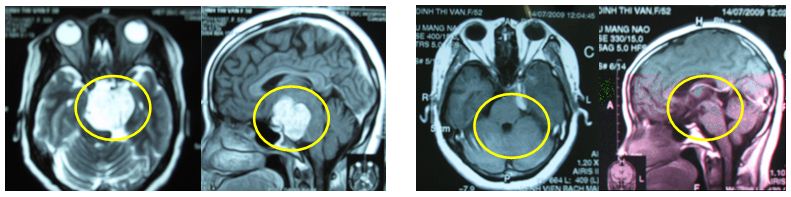

Bệnh nhân Đinh T , V, 52 tuổi, vào viện vì đau đầu nhiều, nôn, tê yếu nửa người trái, chẩn đoán u màng não nền sọ chèn ép thân não, dây thị giác. Bệnh nhân được xạ phẫu Gamma Knife liều 18 Gy. Trước điều trị: u màng não nền sọ to, kích thước 3,9 x 4,1 x 4,9 cm, u chèn ép thân não gây yếu tê nửa người trái, đau đầu nhiều, không có khả năng điều trị bằng phương pháp khác.

Sau xạ phẫu bằng dao gamma 24 tháng, u tan gần hết, bệnh nhân hết các triệu chứng đau đầu, tê, yếu nửa người trái; đi lại vận động bình thường.

2. U màng não

Bệnh nhân Nguyễn Đ, T, nam, 32 tuổi

Chẩn đoán: U màng não

Chỉ định: xạ phẫu bằng RGK, liều 20 Gy